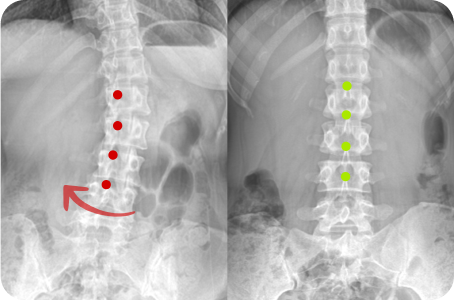

Before & After

해당 사진은 수정없는 실제 치료사진입니다.

환자의 치료결과는 환자의 상태, 치료방법 등에 따라 차이가 발생할 수 있습니다.